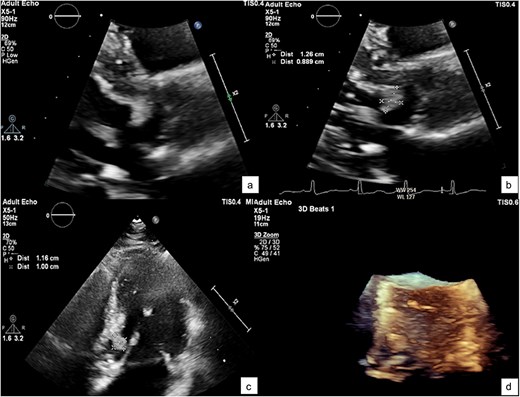

A zoomed-in view of the mass with measurements of 1.2 × 1 × 0.9 cm (a–c) and in 3D echocardiography (d).

He was referred to our hospital for further evaluation by the cardiology and cardiothoracic surgery departments. On admission, he was afebrile with a heart rate of 62 beats per minute, blood pressure of 148/73 mmHg, and respiratory rate of 20 breaths per minute. No abnormalities were noted in any other system. Laboratory findings were unremarkable. An ECG demonstrated normal sinus rhythm. TTE re-evaluation revealed a normal LVEF of 72% with a 1.2 × 1 cm hypermobile cardiac mass attached to the basal anteroseptal wall near the LVOT without evidence of LVOT obstruction; there were no valvular lesions or thrombus seen (Figs 1 and 2). Coronary angiography showed normal coronary vessels. Due to its nature and clinical presentation, the patient was set for early surgical excision of the mass 3 days after admission.